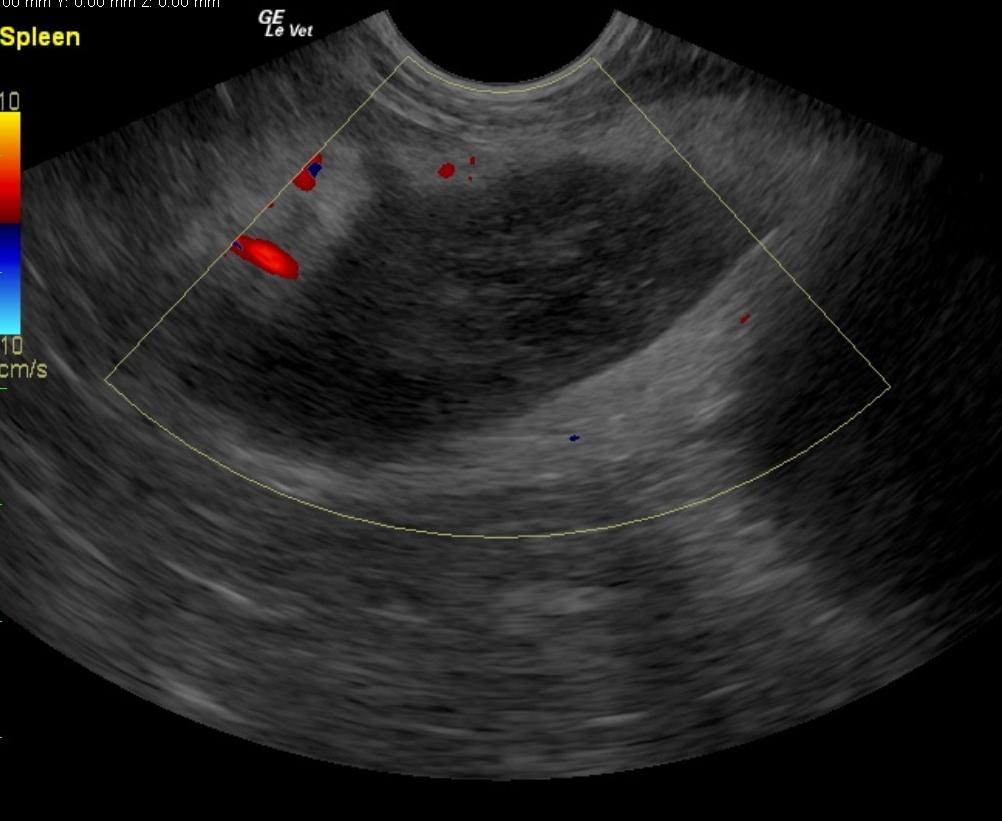

A 7-year-old FS Jack Russell Terrier with a history of regulated hypothyroidism, was presented for vomiting, lateral recumbency, and abdominal pain following ingestion of a ham bone. The owner also reported that the patient had been showing polyuria/polydipsia prior to the incident. On physical examination, the patient was laterally recumbent and very painful. CBC showed polycythemia and low band neutrophils. On blood chemistry, mildly elevated BUN, elevated creatinine, elevated ALP activity, elevated lipase, severely elevated ALT activity, and elevated cPLI were evident. A hemorrhagic diathesis was present on coagulation panel. Blood pressure was 145/80. The patient was treated with I.V. fluids, hetastarch, morphine/ketamine drip, fresh frozen plasma, antibiotics, and placed in an oxygen cage. On survey abdominal radiographs, bony fragments were evident in the gastrointestinal tract. The patient was sedated, given an enema, and a large piece of bone was produced. After 42 hours on therapy the patient developed dyspnea, which, on survey thoracic radiographs, was suggestive of fluid overload. Lasix was administered, which resulted in resolution of the dyspnea. Recheck blood chemistry showed hypoproteinemia, elevated ALP activity, hyperglycemia, improved azotemia, and normalization of cPLI. Physical examination, after 72 hours of supportive care, found the patient BAR and ambulatory, not interested in food, and still extremely painful upon palpation of the right mid-abdomen. Syringe feedings were started, which were well tolerated with no vomiting. However, the following morning the patient was less bright and more painful in the abdomen.